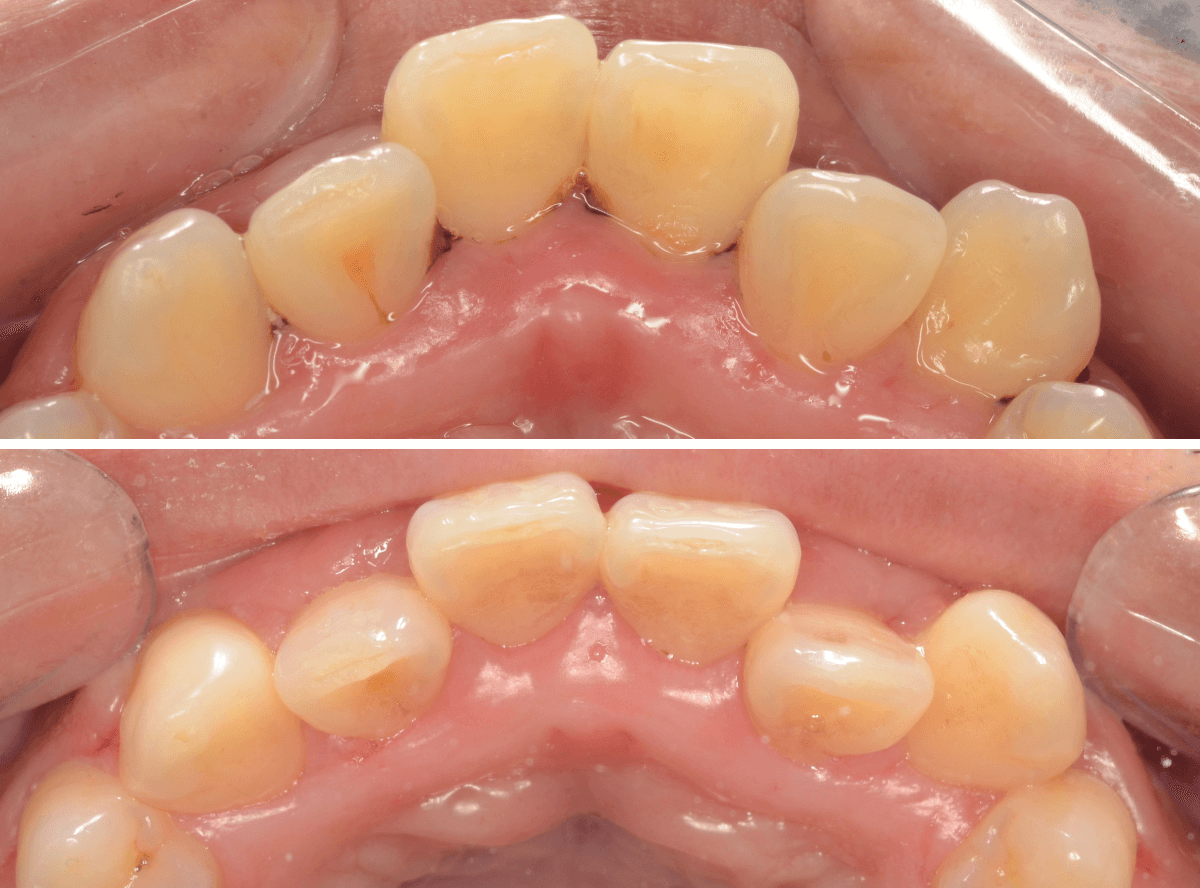

Case.3 縁下歯石除去後、3か月の状況

今回は、下の前歯の縁下歯石を除去した後、3か月後のメンテナンスにいらっしゃった方の治療前後です。

前側から見た所です。

とても綺麗に歯肉が治っているのがわかると思います。

歯石除去が終わったあとも、頑張ってお手入れしているのがうかがえます。

歯石除去だけでは、ここまで綺麗には治りません。

裏側の歯肉の状態も大きく変わりました。

年齢もお若い方なので、歯肉の回復も早いです。

ある程度まで歯周病が進行してしまいますと、完全に歯肉が元に戻るのは難しくなってしまいます。

本格的な歯周病になる前に治療を受けていただけて、本当に良かったと思います。

あとは、油断せずに持続していただきたいと思っています。